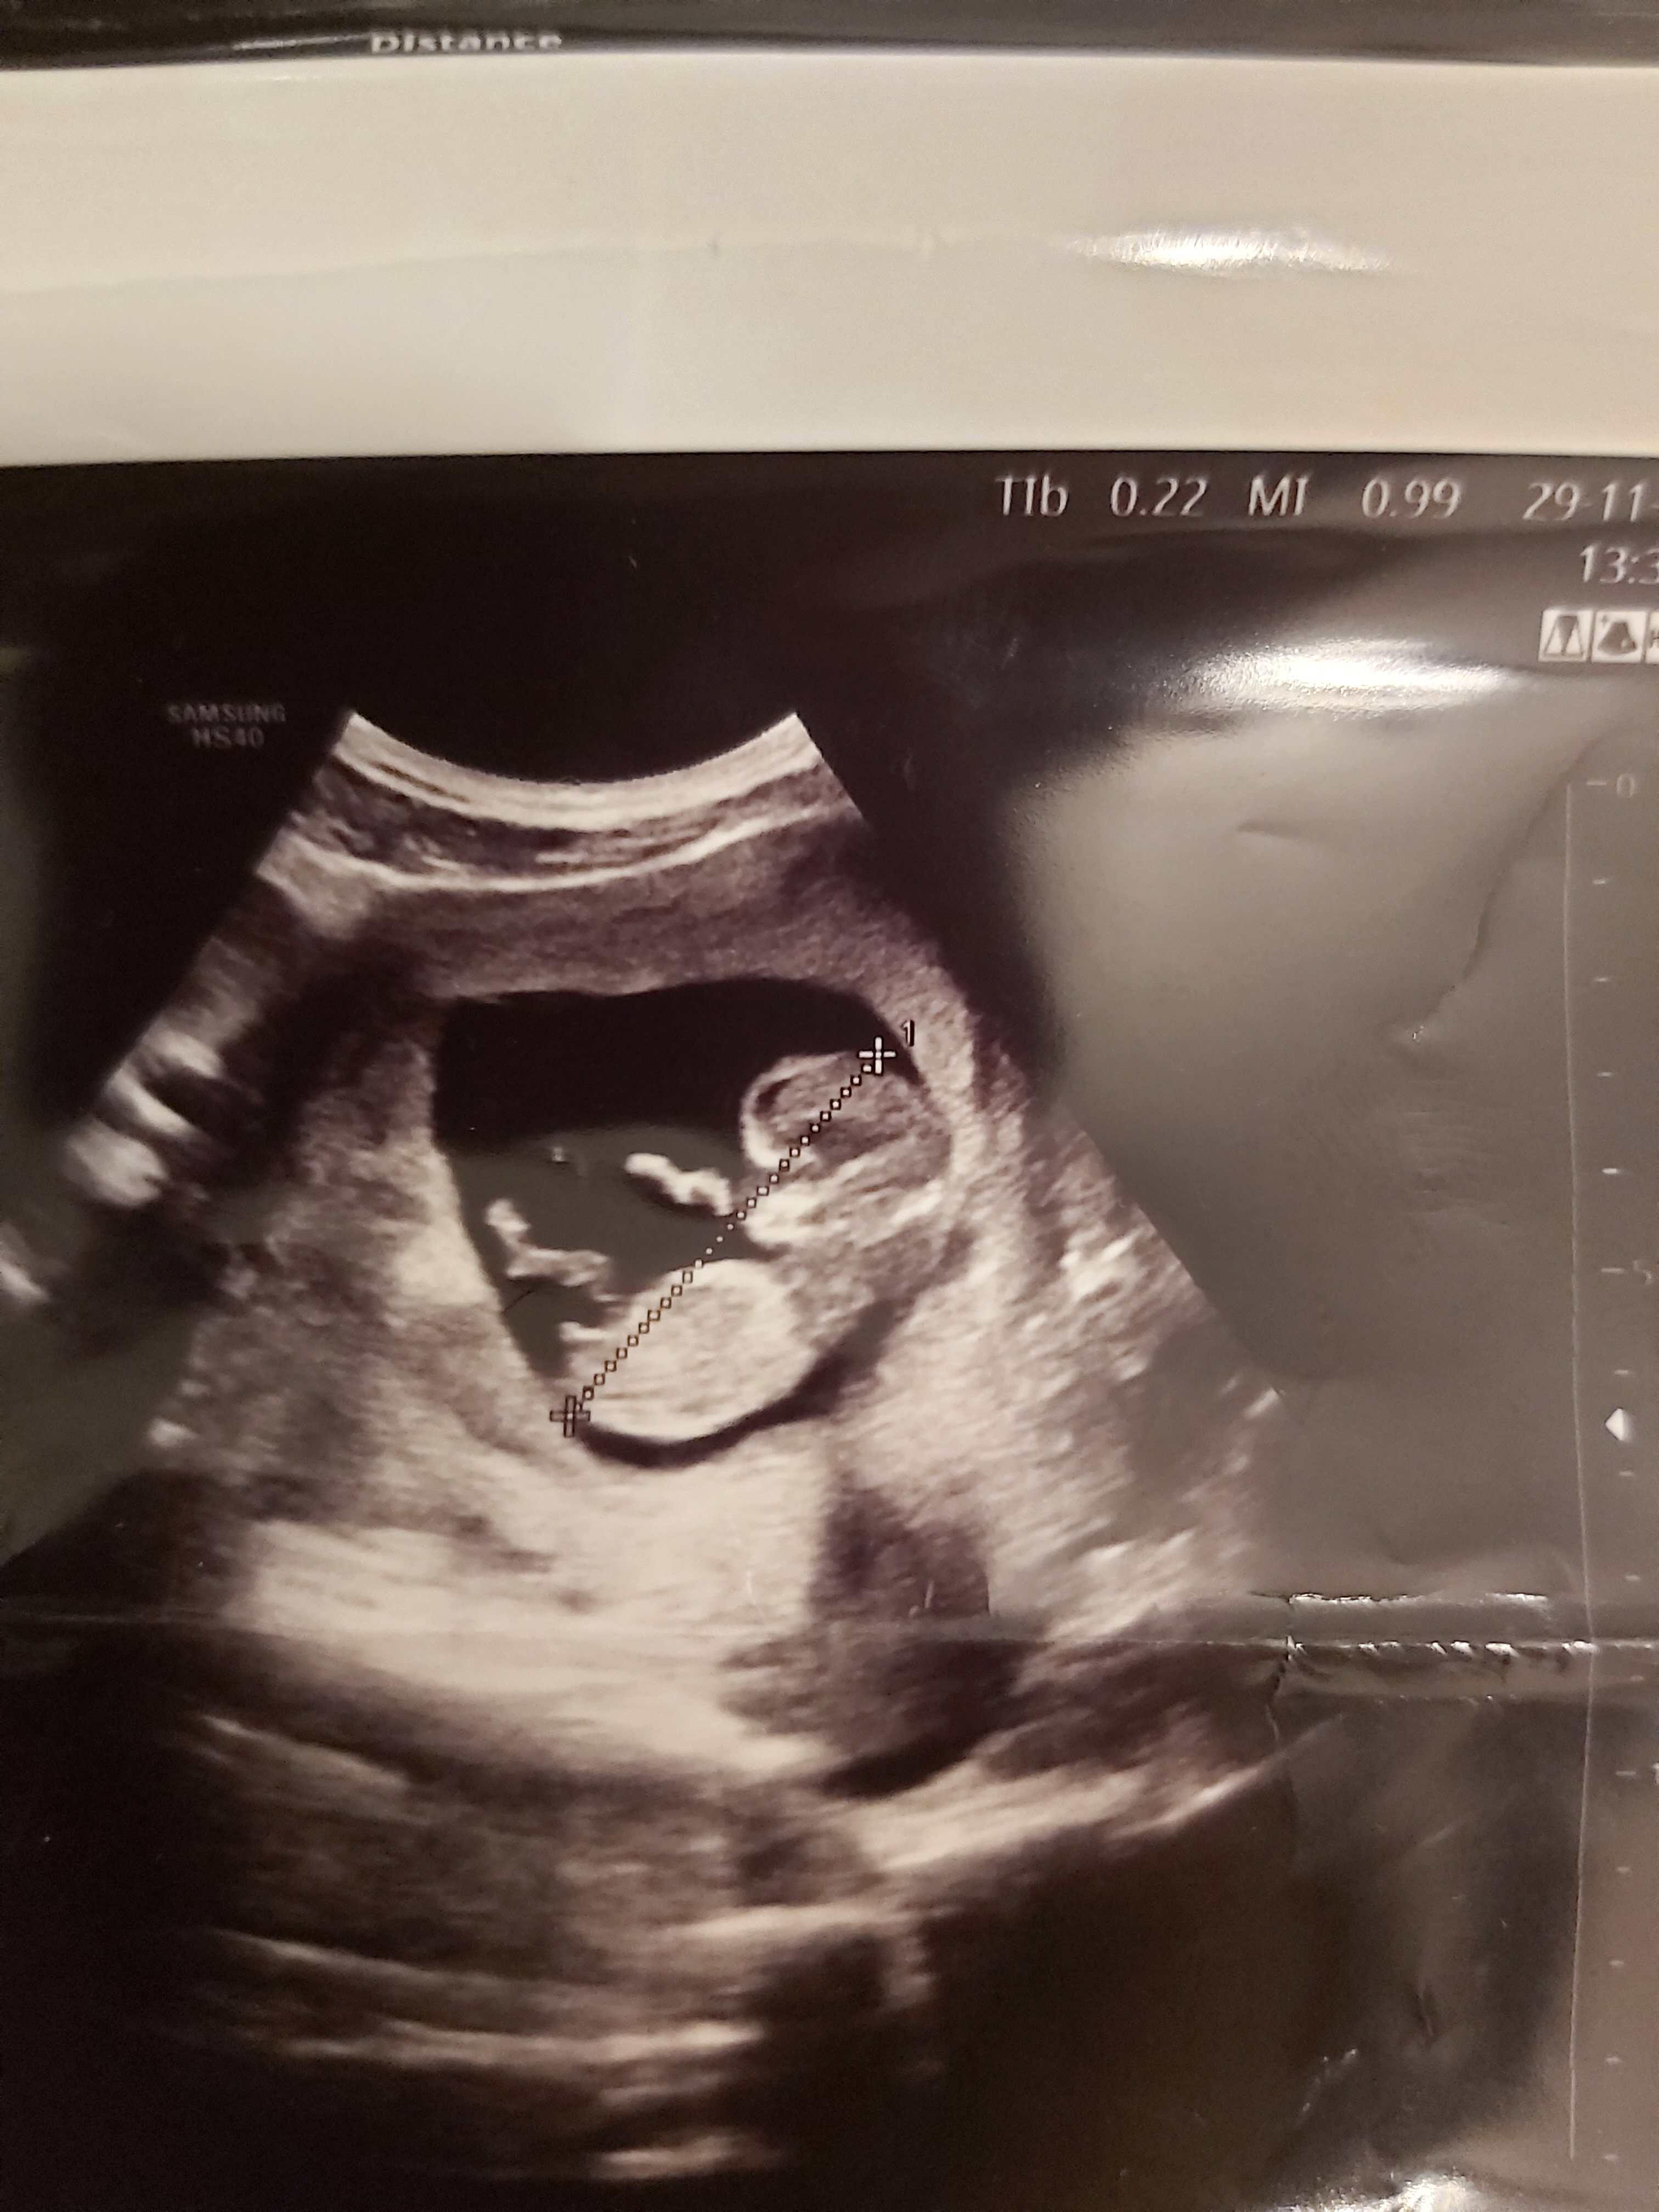

A Ayşe08 Yeni Üye Üye 1 Aralık 2019 #17 Merhabalar, 11+4 usg ye nub teorisine gore cinsiyet tahmininde bulunur musunuz ?